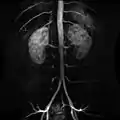

صور إضافية

Contrast enhanced MRA of the abdominal aorta demonstrating normal paired arteries.